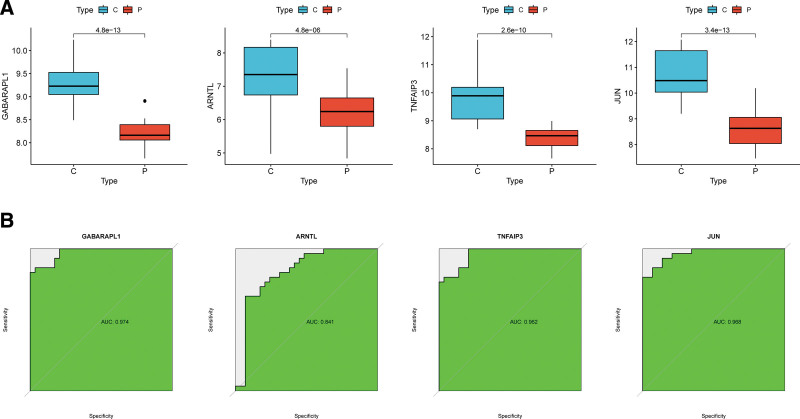

Three ML algorithms simultaneously employed for the identification of feature genes, SVM-RFE algorithm selected 8 genes from ferroptosis-related hub genes (Fig. 4A), LASSO algorithm identified eleven genes (Fig. 4B) and RF algorithm provided ten genes (Fig. 4C). Taking the intersection of the results of genes selection by the 3 ML methods, we ultimately obtained 4 feature genes: GABARAPL1, TNFAIP3, ARNTL, and JUN (Fig. 4D). Followed correlation analysis among the expression of the 4 genes all showed positive correlations, suggesting an underlying synergy of the biological impact of the 4 genes (Figure S1, http://links.lww.com/MD/K714). We then performed difference analysis in merge data and reconfirmed the down-regulation of expression of the 4 genes in OA (Fig. 5A). The area under curve (AUC) of ROC analysis was 0.974 for GABARAPL1, 0.841 for ARNTL, 0.962 for TNFAIP3, and 0.968 for JUN (Fig. 5B).